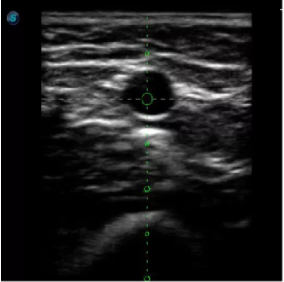

4  置管專用探頭

實時觀察穿刺針進入血管的全過程,方便操作及較短的穿刺路徑,智能進針尺寸提示,讓置管工作更加輕松,高效。

不同進針路徑